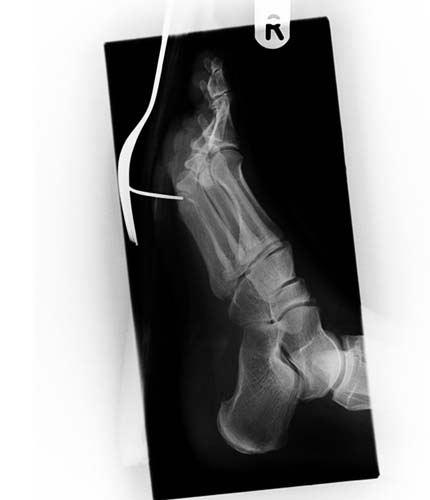

Bir hastanın ayağına saplanmış çatal...